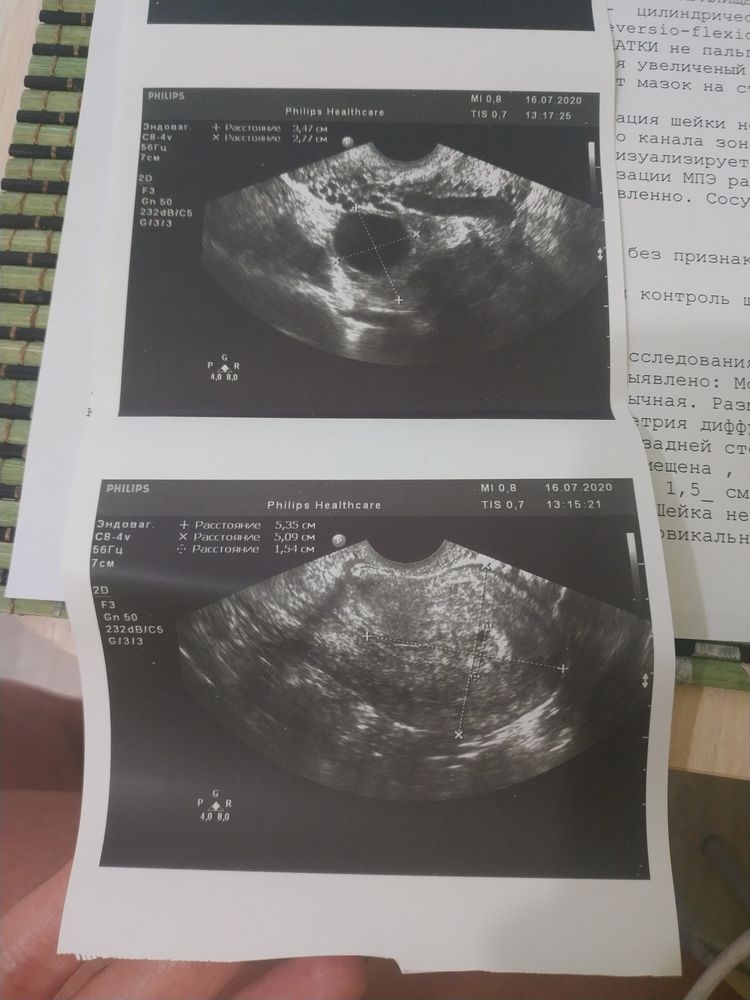

писала длинный пост, но он не сохранился, поэтому пишу коротко. Была на УЗИ сегодня, сказали есть плодное яцр, пустое. Месячные приходили во время, но были странные. Первый день месяца 6 июля. Цикл регулярный. Врач увидела овуляцию в левом яичнике. Сказала что беременность, кисты нет. Через неделю прийти повторно. Почитала интернет, и как бы засомневалась. Ведём ППА. Несколько лет. Не так давно планировали беременность но не получалось. Забили на это дело. И тут сидим и места не найдем).

Тест отрицательный. Фото с УЗИ прикладываю.

Если это ПЯ, то размер гораздо меньше, чем 1,5см. И насколько я поняла по фото, 1,5 см у вас в заключении узи указано совсем другое, возможно м-эхо. Размер очень маленький, чтобы гадать пустое оно или нет.

На последнем фото узи похоже выделено плодное яйцо (или что там) в 1,54см, это 15мм. Довольно большое. Сдайте хгч, в динамике. И тест уже должен быть положительный. Если оба анализа отрицательные, вновь идите к врачу.

Если это плодное яйцо, то размеры большие, для такого ПЯ уже должен быть эмбрион и тесты должны гореть полосками